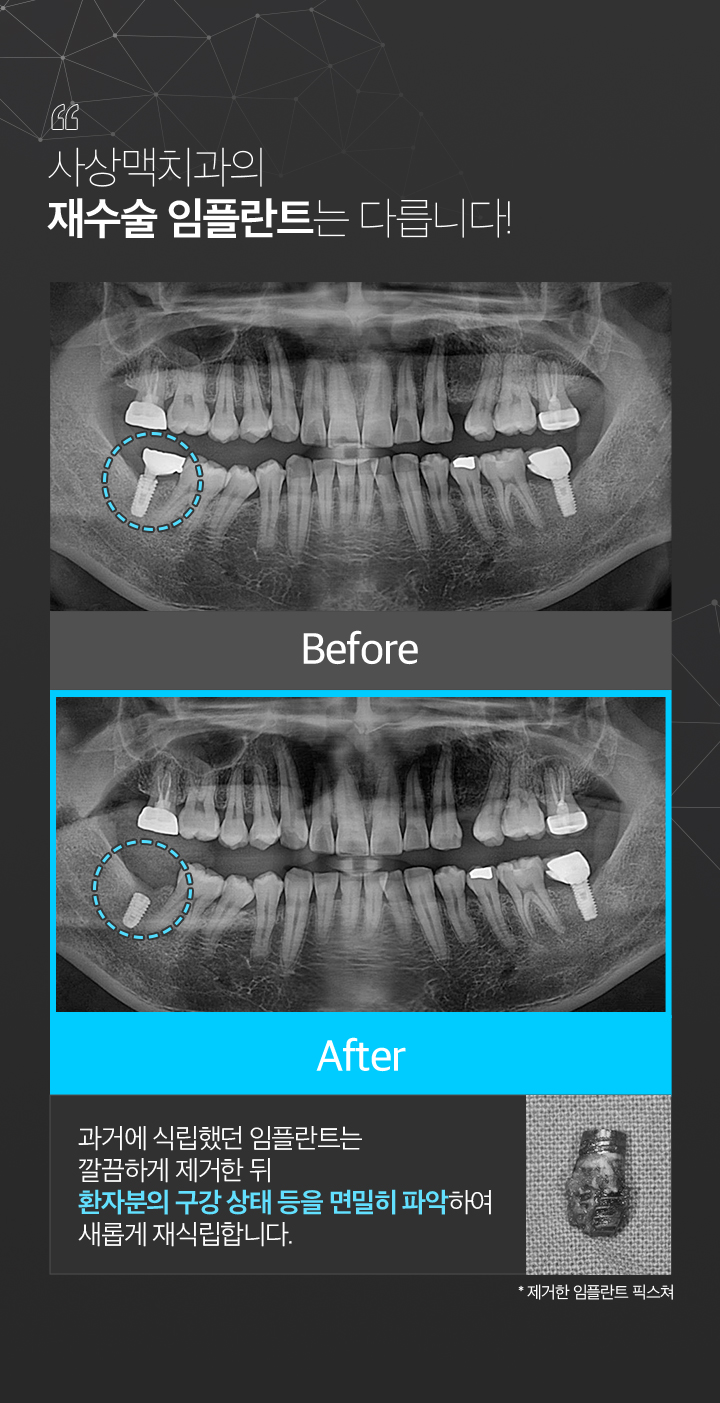

임플란트재수술